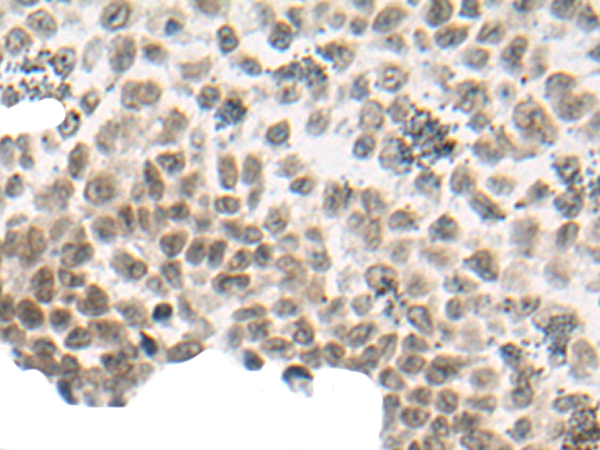

分类: 科研抗体货号: P13129别名: AMID; PRG3应用: IHC反应种属: Human, Mouse